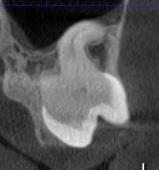

Коли коріння «ховає сюрпризи» - Корені зубів часто мають складну кривизну, гачкоподібні закручення або розгалуження, які на звичайному 2D-знімку накладаються один на одного, створюючи ілюзію прямого каналу. На плоскій картинці неможливо побачити реальний об'єм та напрямок вигину, що критично важливо при видаленні «зубів мудрості» або ендодонтичному лікуванні. КТ MyRay дає змогу лікарю заздалегідь побачити 3D-геометрію кожного кореня, оцінити його близькість до нижньощелепного нерва чи гайморової пазухи та підібрати правильну тактику роботи. Це мінімізує ризики поломки інструменту в каналі або травмування сусідніх структур, перетворюючи складну хірургію на прогнозовану процедуру.